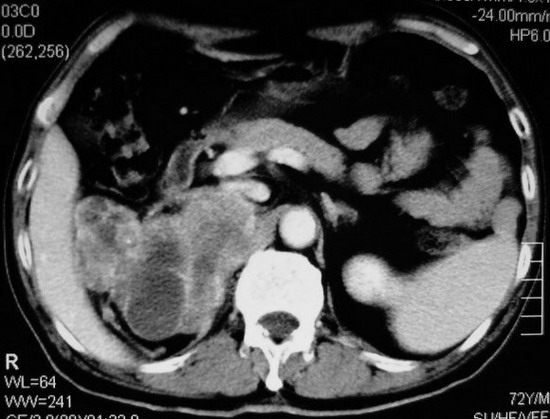

以下是引用杀毒软件在2008-11-17 19:15:00的发言:[br]考虑------右肾癌合并肾静脉---同侧肾上腺受侵可能性大

以下是引用zjzjr在2008-11-17 20:45:00的发言:[br]考虑------右肾癌合并肾静脉---同侧肾上腺受侵可能性大及腹膜后淋巴结转移.